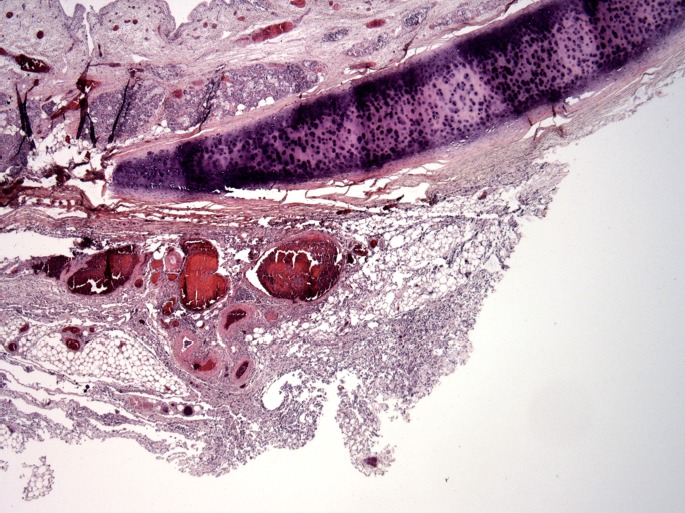

Image 8.

Case 1: Trachea with acute inflammation of the adventitia (H&E, x40).

Image 9.

Case 1: Trachea with acute inflammation of the adventitia (H&E, x200).